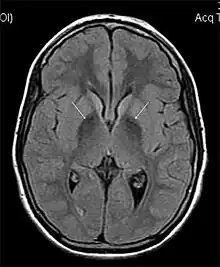

| MRI hypointensity (white arrows) in the globus pallidi that indicates the presence of iron deficiencies which would be seen in a diagnosis of Aceruloplasminemia | |

Diagnosis of this disorder depends on blood tests demonstrating the absence of serum ceruloplasmin, combined with low serum copper concentration, low serum iron concentration, high serum ferritin concentration, or increased hepatic iron concentration. MRI scans can also confirm a diagnosis; abnormal low intensities can indicate iron accumulation in the brain.[5]